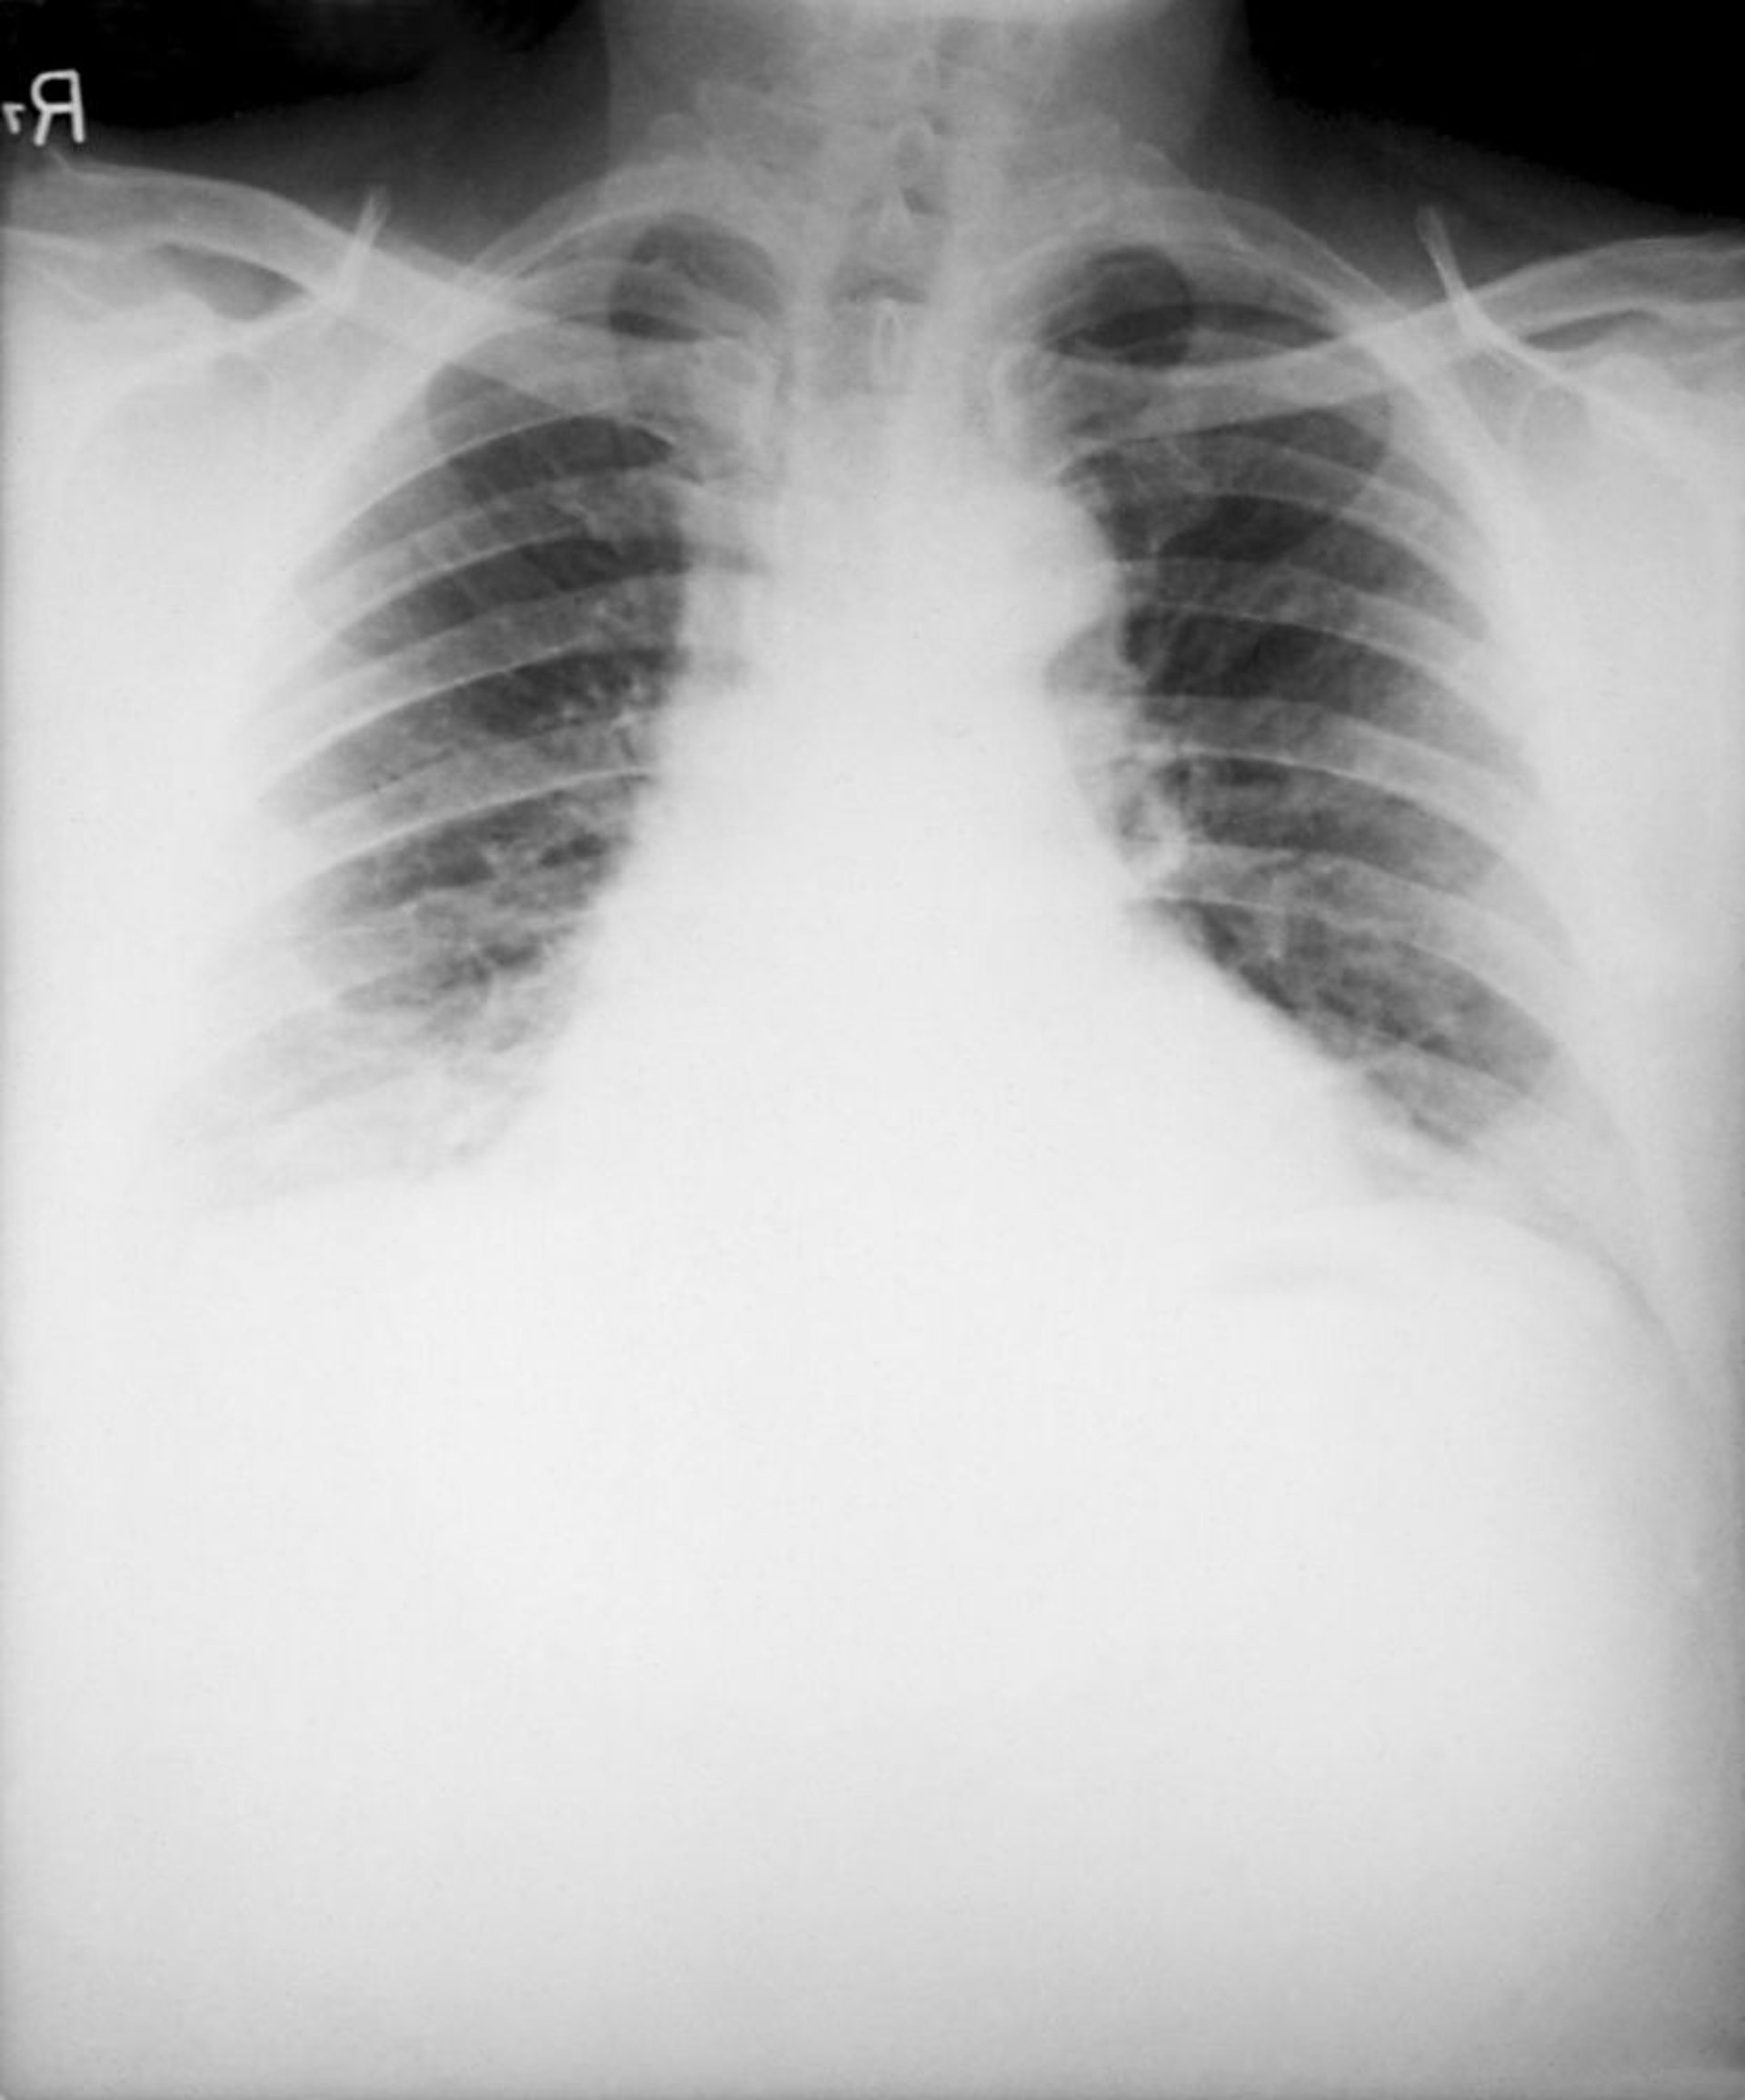

Antraz (por inalação)

Achados típicos da inalação de antraz na radiografia de tórax são alargamento do mediastino por linfadenite mediastinal necrosante hemorrágica e derrame pleural bilateral. Infiltrados pneumônicos são incomuns.

Imagem cedida por cortesia da Biblioteca de Imagens de Saúde Pública dos Centros de Controle e Prevenção de Doenças.